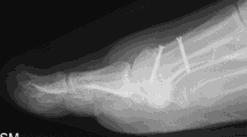

Lapidus (metatarsal cuneiform fusion)

This involves a fusion of the first metatarsal cuneiform joint, allowing the first metatarsal to be rotated back into a straight position. It is normally reserved for severe deformities. Once the corrected position has been obtained it is usually maintained with a plate and screws.

Possible risks with a Lapidus

Due to the corrective power of this procedure, there is a risk of overcorrection of the bunion, which may result in poor alignment with associated pain and arthritis in the big toe joint. A failure of the two bones to unite (non-union) can result in poor alignment and pain. In our department the audited risk of a non-union is 2%, which is lower than the average reported rate of 3.8%. A non-union may require revision surgery.